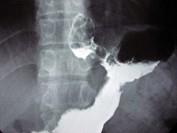

问题 男,56岁,胸骨后不适3个月,吞咽时有异物感,X线检查如图,最可能的诊断是 ( )

选项 A.食管癌 B.食管腺瘤 C.贲门腺癌 D.胃癌 E.食管下段溃疡

答案 C